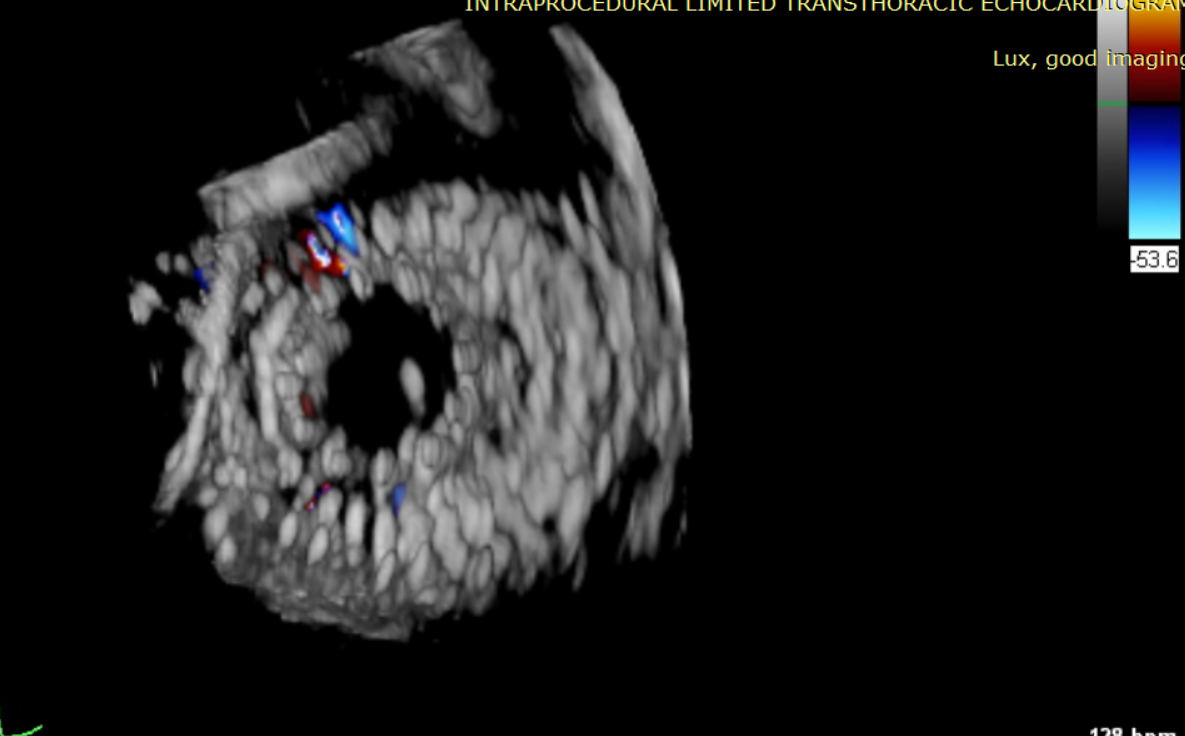

術前超聲提示大量三尖瓣反流

術中輸送器在超聲引導下調整位置

術后超聲提示無瓣周漏

術后超聲提示僅殘余輕微瓣周漏

術后Azeem Latib教授對LuX-Valve Plus經血管三尖瓣置換系統的器械性能和治療效果大為稱贊,并且認為LuX-Valve Plus的手術體驗非常好。從治療效果來看,術后即刻超聲顯示三尖瓣反流幾乎完全消失,血流動力學改善顯著,患者恢復快。在面對復雜解剖結構、超聲影像質量不佳、有起搏導線干擾時,Lux-Valve Plus也體現了極強的適應性。Thomas Modine教授參與了術中指導,他同樣再次肯定了LuX-Valve Plus術中操作的便捷性,認為LuX-Valve Plus容錯率高,對術中影像的依賴小,并表達了后期希望可以更多地應用LuX-Valve Plus三尖瓣置換系統于臨床實踐,讓更多的三尖瓣重度反流患者盡早獲益,改善預后。